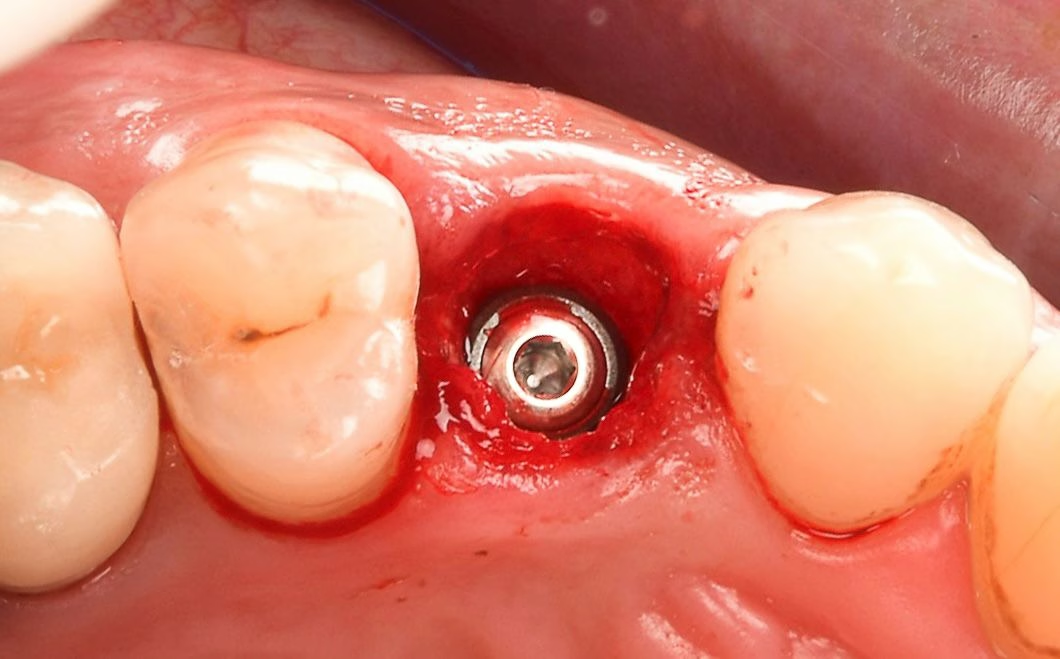

La Prothèse Transvissée (Vissée)

La sécurité de la réversibilité. Privilégiée pour son absence totale de ciment de scellement (éliminant le risque de péri-implantite liée au ciment), elle garantit un accès facile pour la maintenance.

Nos logiciels permettent de concevoir des puits d'accès angulés pour préserver l'esthétique vestibulaire, même en cas d'axes implantaires défavorables.

Galerie de cas en Implantologie

Apercu de cas implantaires sur mise en charge immédiate. Entre la prise d empreinte et la pause chirurgicale.